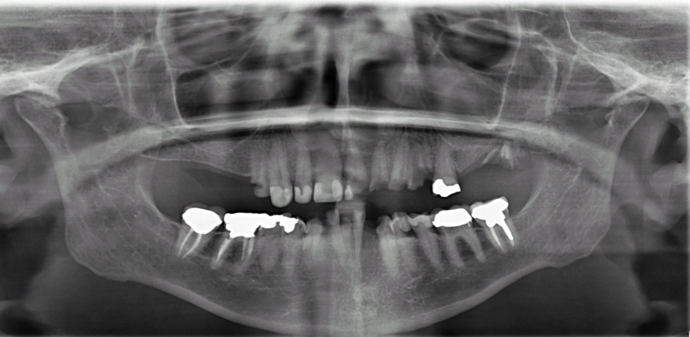

This retired professional had really healthy teeth until she was placed on several medications which caused dry mouth and quickly deteriorated her teeth beyond repair. She was extremely dissatisfied with her smile and wanted the best possible result. She had been offered snap on implant dentures by multiple dentists but she disliked the idea of removing her teeth at night and was therefore treated with full arch fixed bridges supported by implants all done in one day!

Procedures : extractions, implants, All on 4 , Teeth in a day, no bone grafting and full mouth reconstruction with monolithic zirconia bridges.